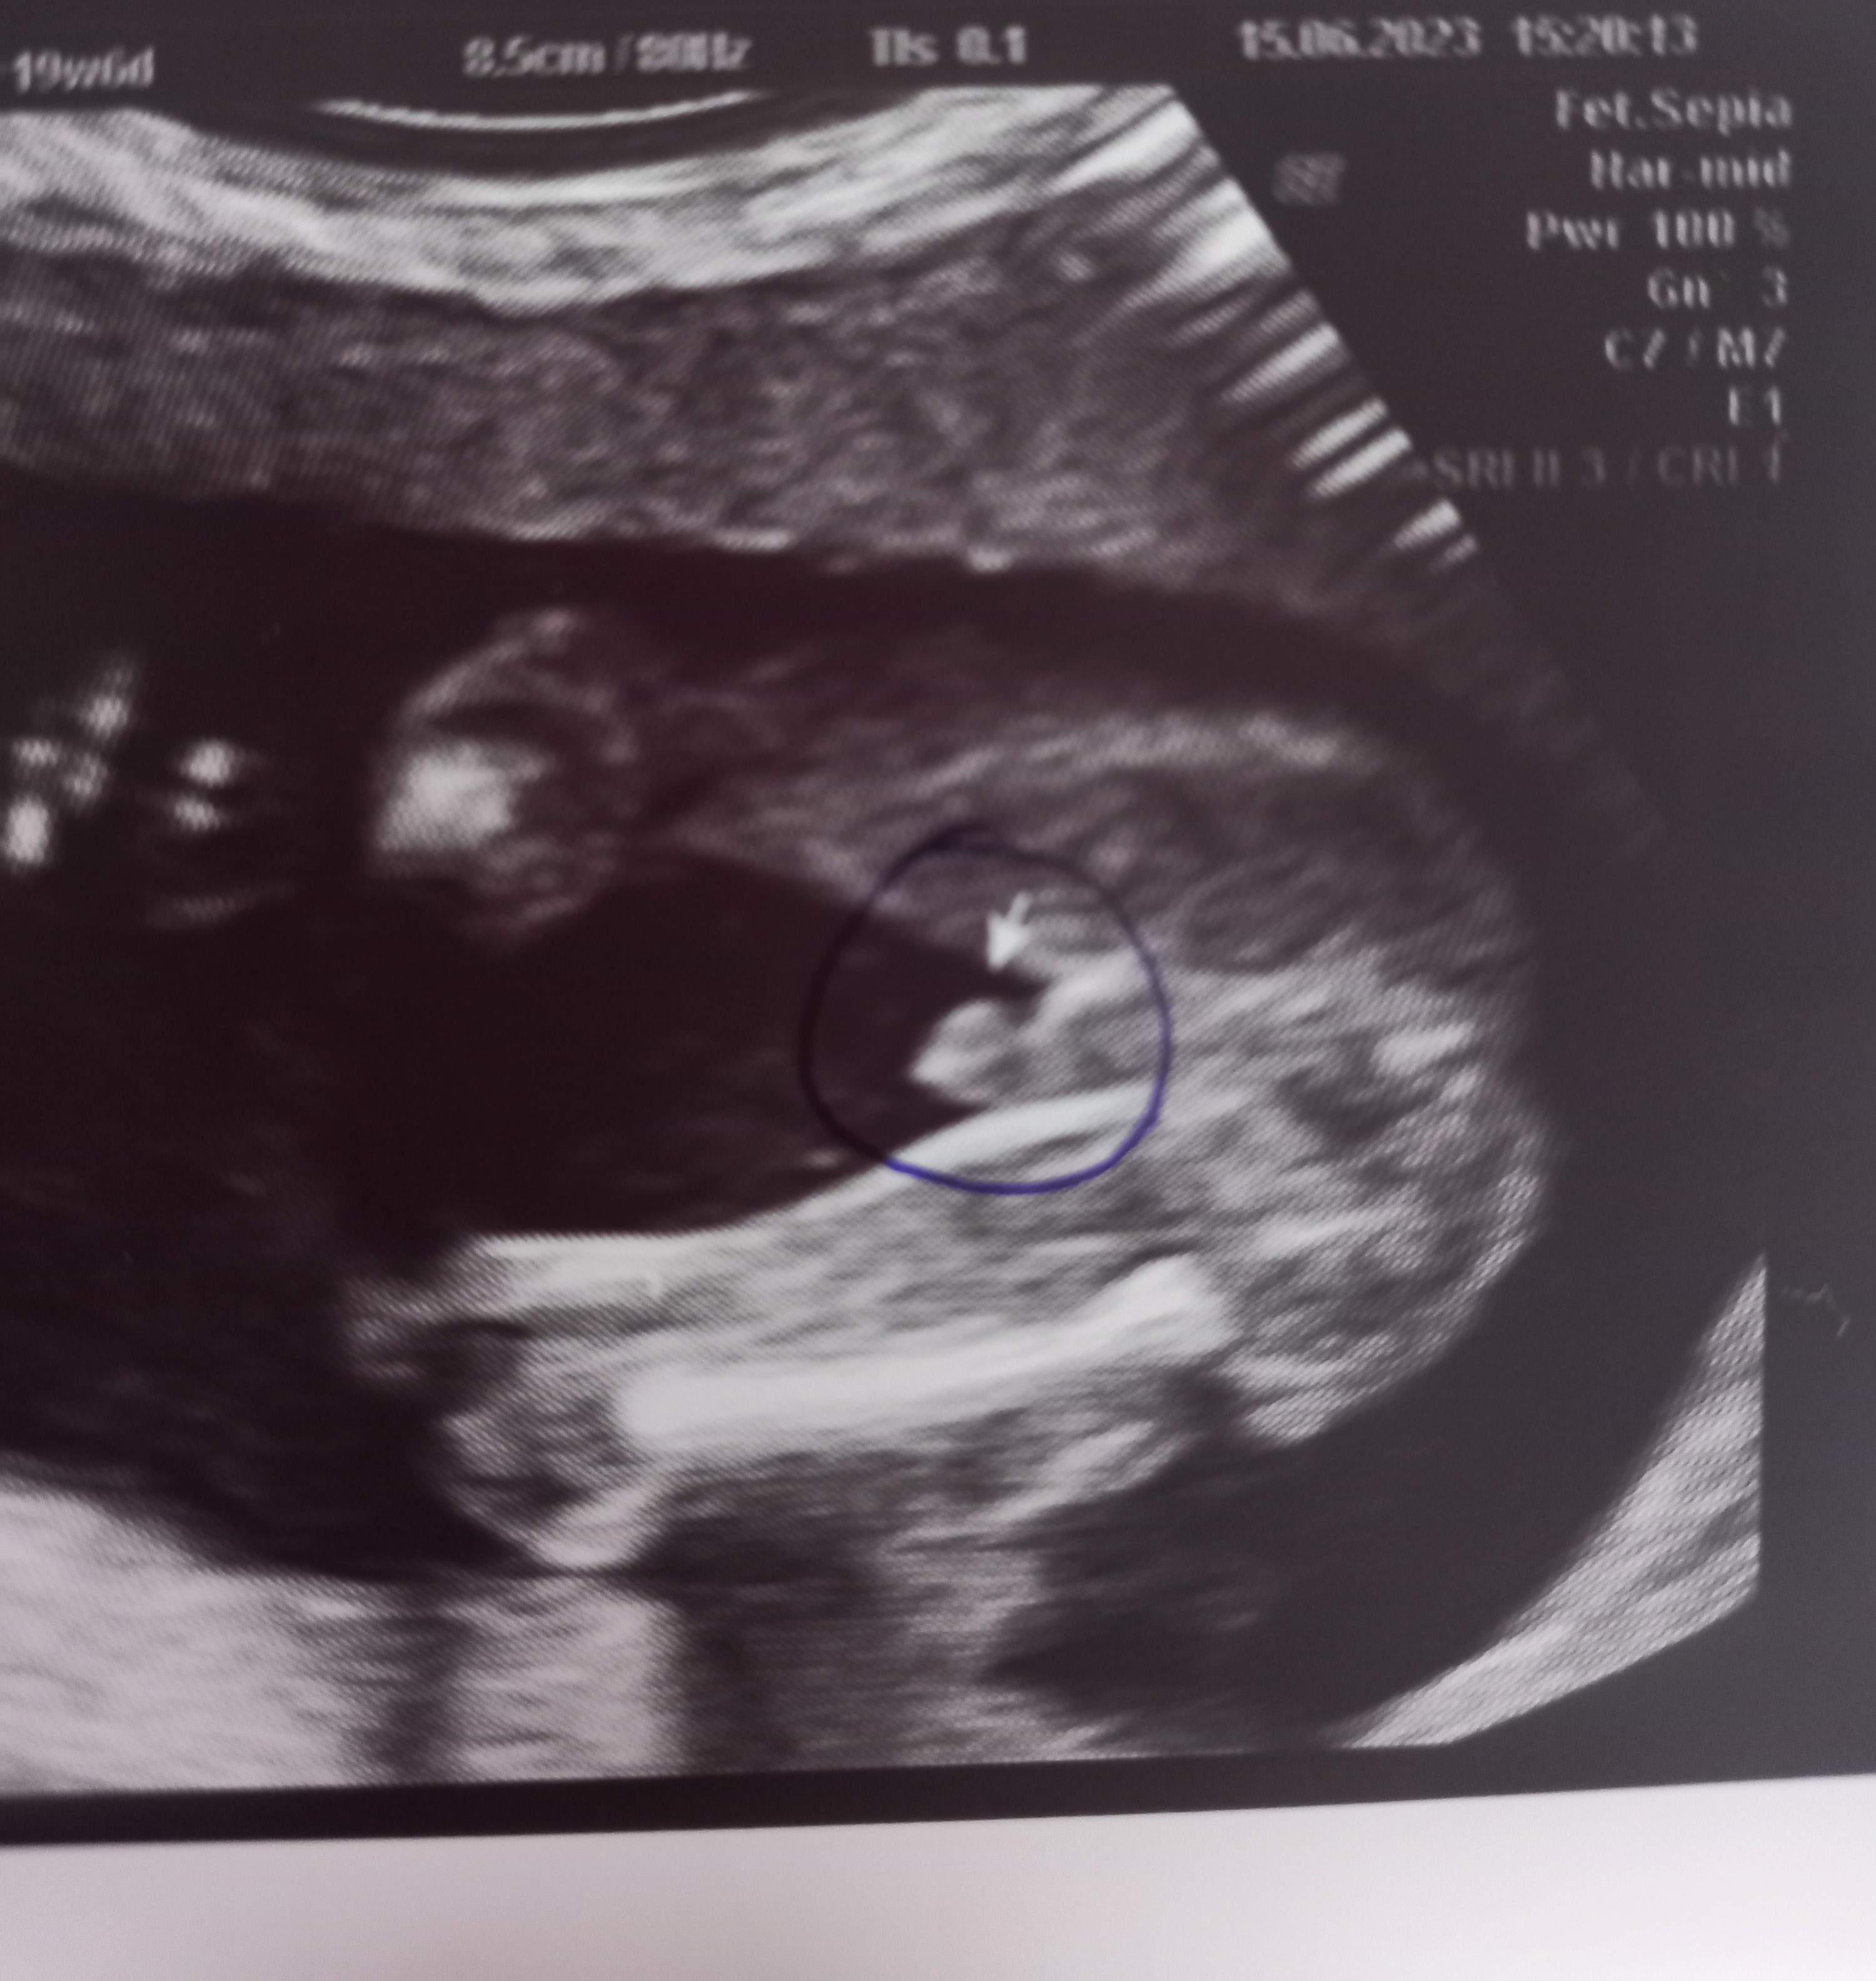

Wyrostek płciowy na usg

Dzięki za odpowiedź 🙃🙃 wg mnie wyrostek u mojego to może być ta biała kreska 🙉 zobaczymy najważniejsze by było zdrowe ale człowiek już by chciał coś kupić dedykowanego pod płeć 🥹

Załączniki

• 20230615_154938.jpg

20230615_154938.jpg

1,6 MB · Wyświetleń: 949